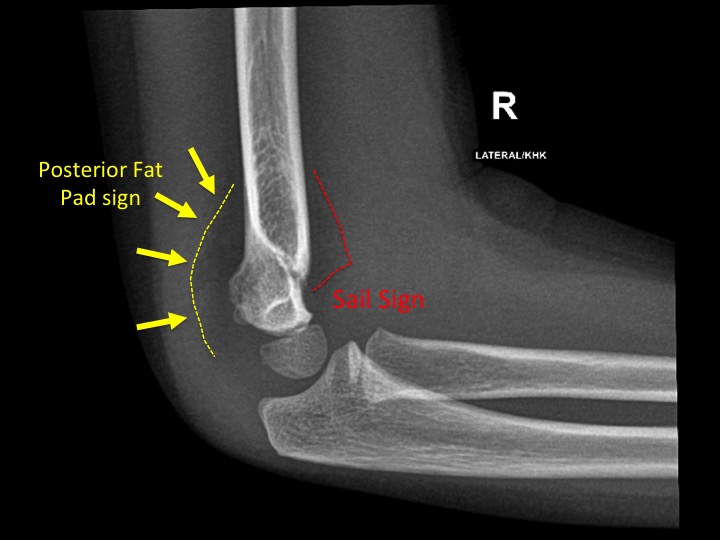

Answer: B) Joint effusion — radial head fracture

Explanation: The “sail sign” (anterior fat pad elevation) and posterior fat pad visibility on an elbow X-ray suggest intra-articular effusion, often due to an occult radial head fracture in adults (or supracondylar fracture in children).

A) is incorrect as a visible posterior fat pad is never normal, it indicates effusion.

C) is incorrect because olecranon dislocations are uncommon and usually show obvious bone displacement.

D) is incorrect because tendon rupture doesn’t typically cause joint effusion with fat pad signs.

E) is incorrect because radial head dislocation is more often seen in children (nursemaid’s elbow) and would be visible as joint malalignment.